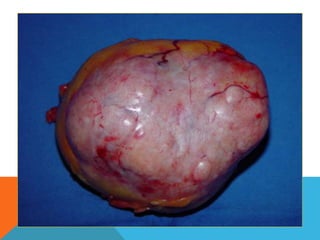

El paciente presentó síntomas de sangrado digestivo y pérdida de peso. Exámenes revelaron gastritis crónica asociada a H. pylori. Un tumor fue descubierto en una colonoscopia normal. La cirugía removió un tumor fibroide solitario, una rara neoplasia mesenquimal que usualmente crece lento y tiene bajo potencial de malignidad. El pronóstico después de la remoción quirúrgica es generalmente bueno.